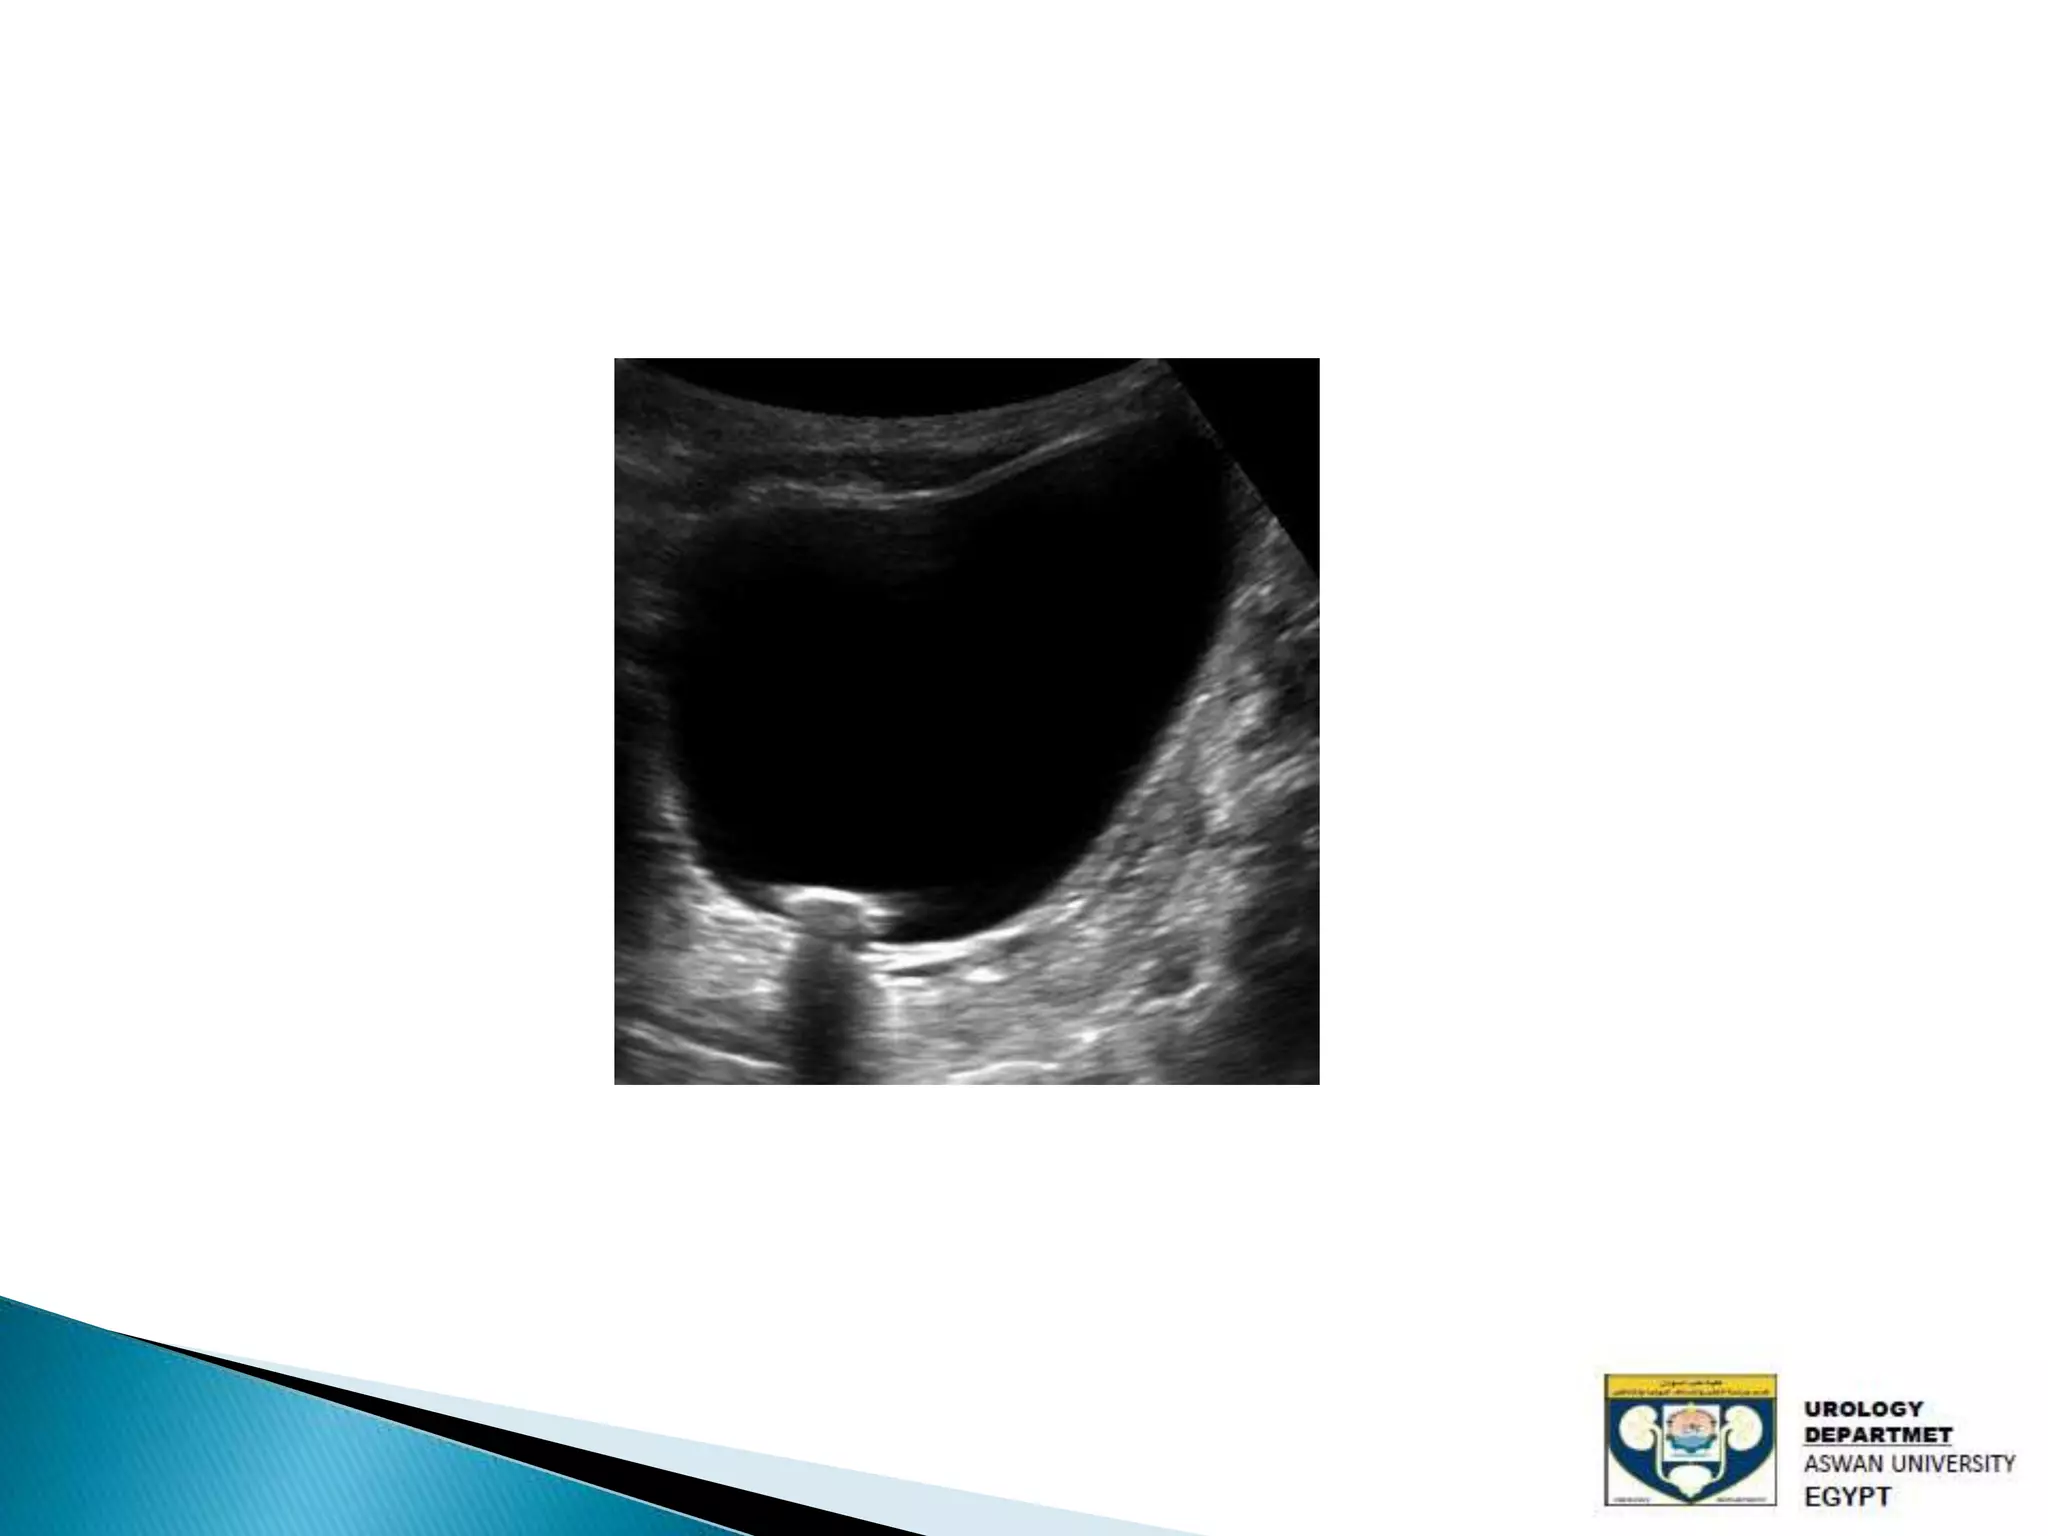

The document discusses urinary tract stones, detailing their types, causes, symptoms, and diagnostic methods. It highlights the risk factors such as infections and obstructions, with men being more commonly affected. Treatment options include various surgical methods, particularly for managing bladder outflow obstruction and lithiasis.